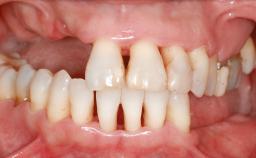

A 45-year-old woman with a completely edentulous maxilla was referred to evaluate the possibility of rehabilitation with an implant-supported prosthesis. This patient was healthy and a non-smoker. She had been wearing a maxillary complete denture opposing a natural mandibular dentition since her twenties. This situation had resulted in progressive resorption of the alveolar ridge, repeatedly creating a need for relining the denture. Twenty years later, despite multiple adaptations and the use of “glues” the denture was unstable and causing the patient psychological and functional discomfort.

Defining Characteristics Fully edentulous upper jaw to be rehabilitated with four or more implants

Defining Characteristics Fully edentulous upper jaw to be rehabilitated with an implant-borne fixed dental prosthesis